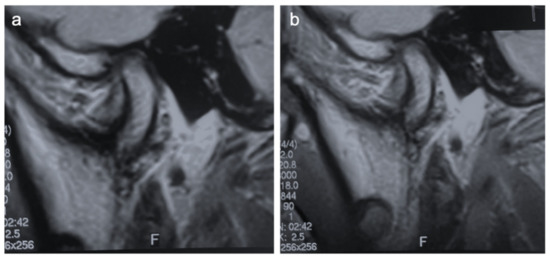

2. Clinical Case